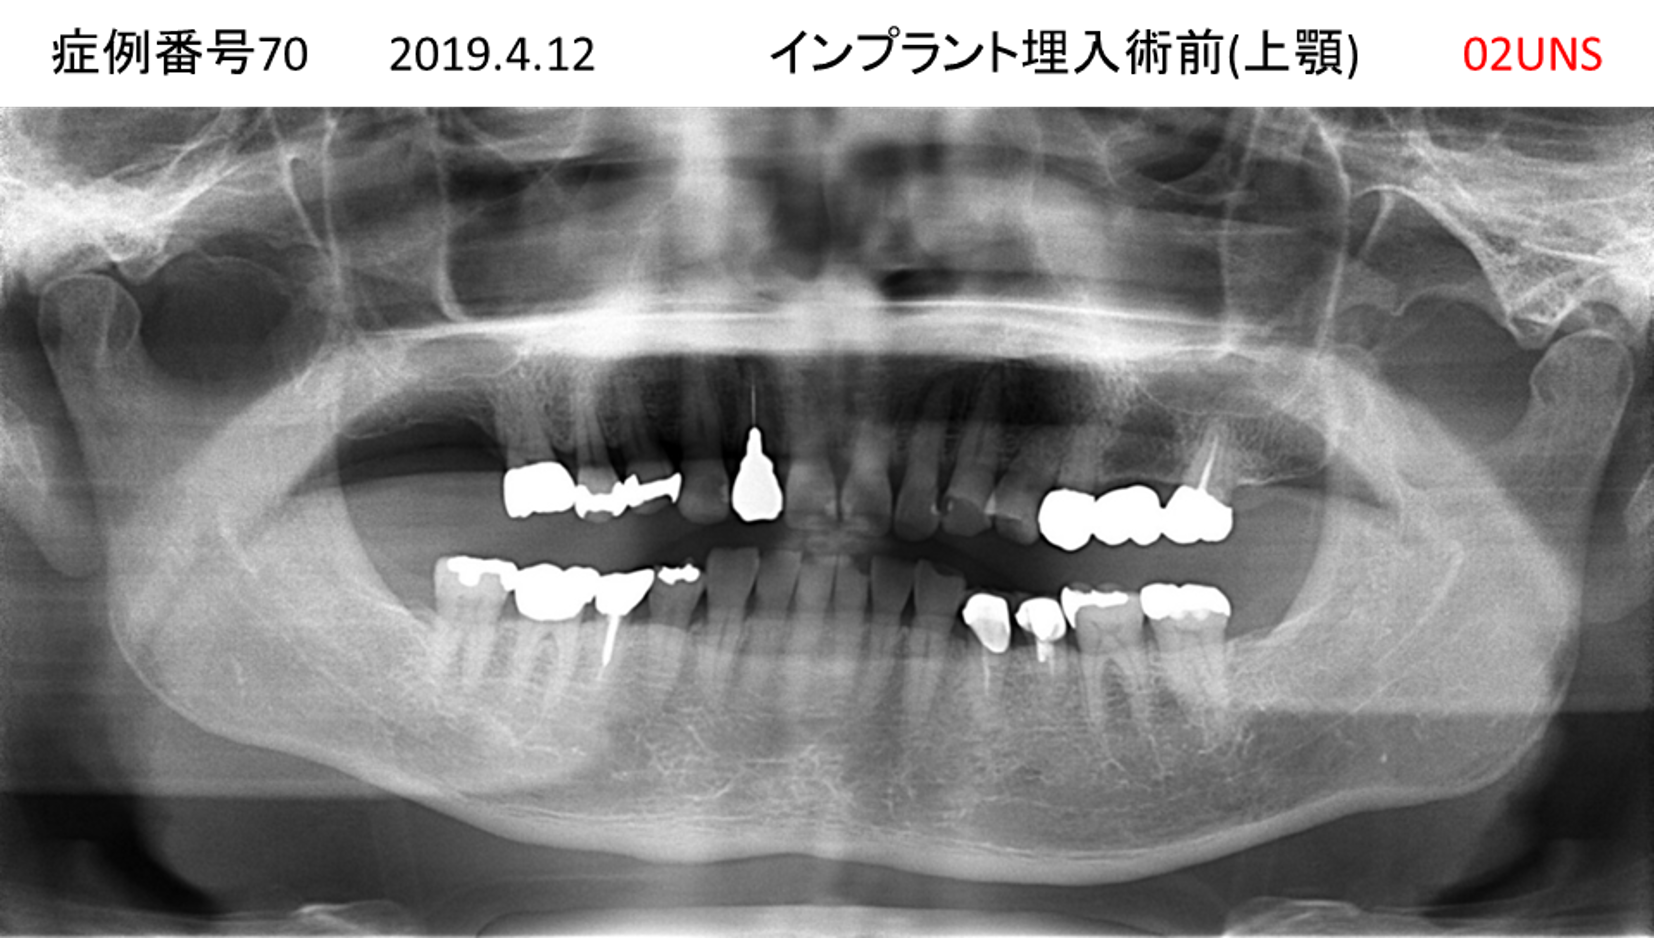

上の前歯が揺れてきてかめない患者様のインプラント症例

| 治療名称 |

インプラント |

| 治療費用 |

440万円+税 |

| 治療期間 |

6か月 |

| 患者さんの症状(主訴) |

上の前歯が揺れてきた。かめない |

| 治療内容 |

サイナスリフト、GBR、インプラント、即時荷重 |

| 治療結果 |

上の前歯の揺れが収まった。奥歯でしっかり噛める。 |

| 治療の注意点(リスク/副作用) |

インプラントが壊れたら再治療が必要 |